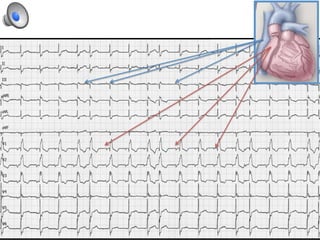

¿Cual es el vaso responsable de este ECG?

A.  Tronco coronario izquierdo

B.  Arteria descendente anterior proximal

C.  Arteria circunfleja

D.  Arteria coronaria derecha

q  T negativas difusas con SDST en aVR

q SDST aVR > V1

q >0.5-1 mm

q IDST en DII, DIII y V4-6

q  Isquemia difusa à NO es sinónimo de TCI (puede

ser E3V y en hipotensión)

q  Elemento de mal pronóstico